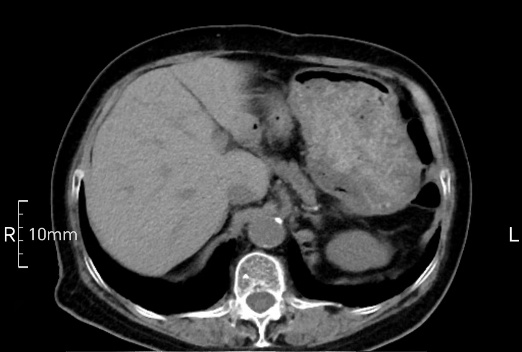

看看下面三幅便知遵醫(yī)囑的重要性。

禁食但檢查前沒(méi)有喝飽,胃未能漲開(kāi),胃壁觀察效果不佳。